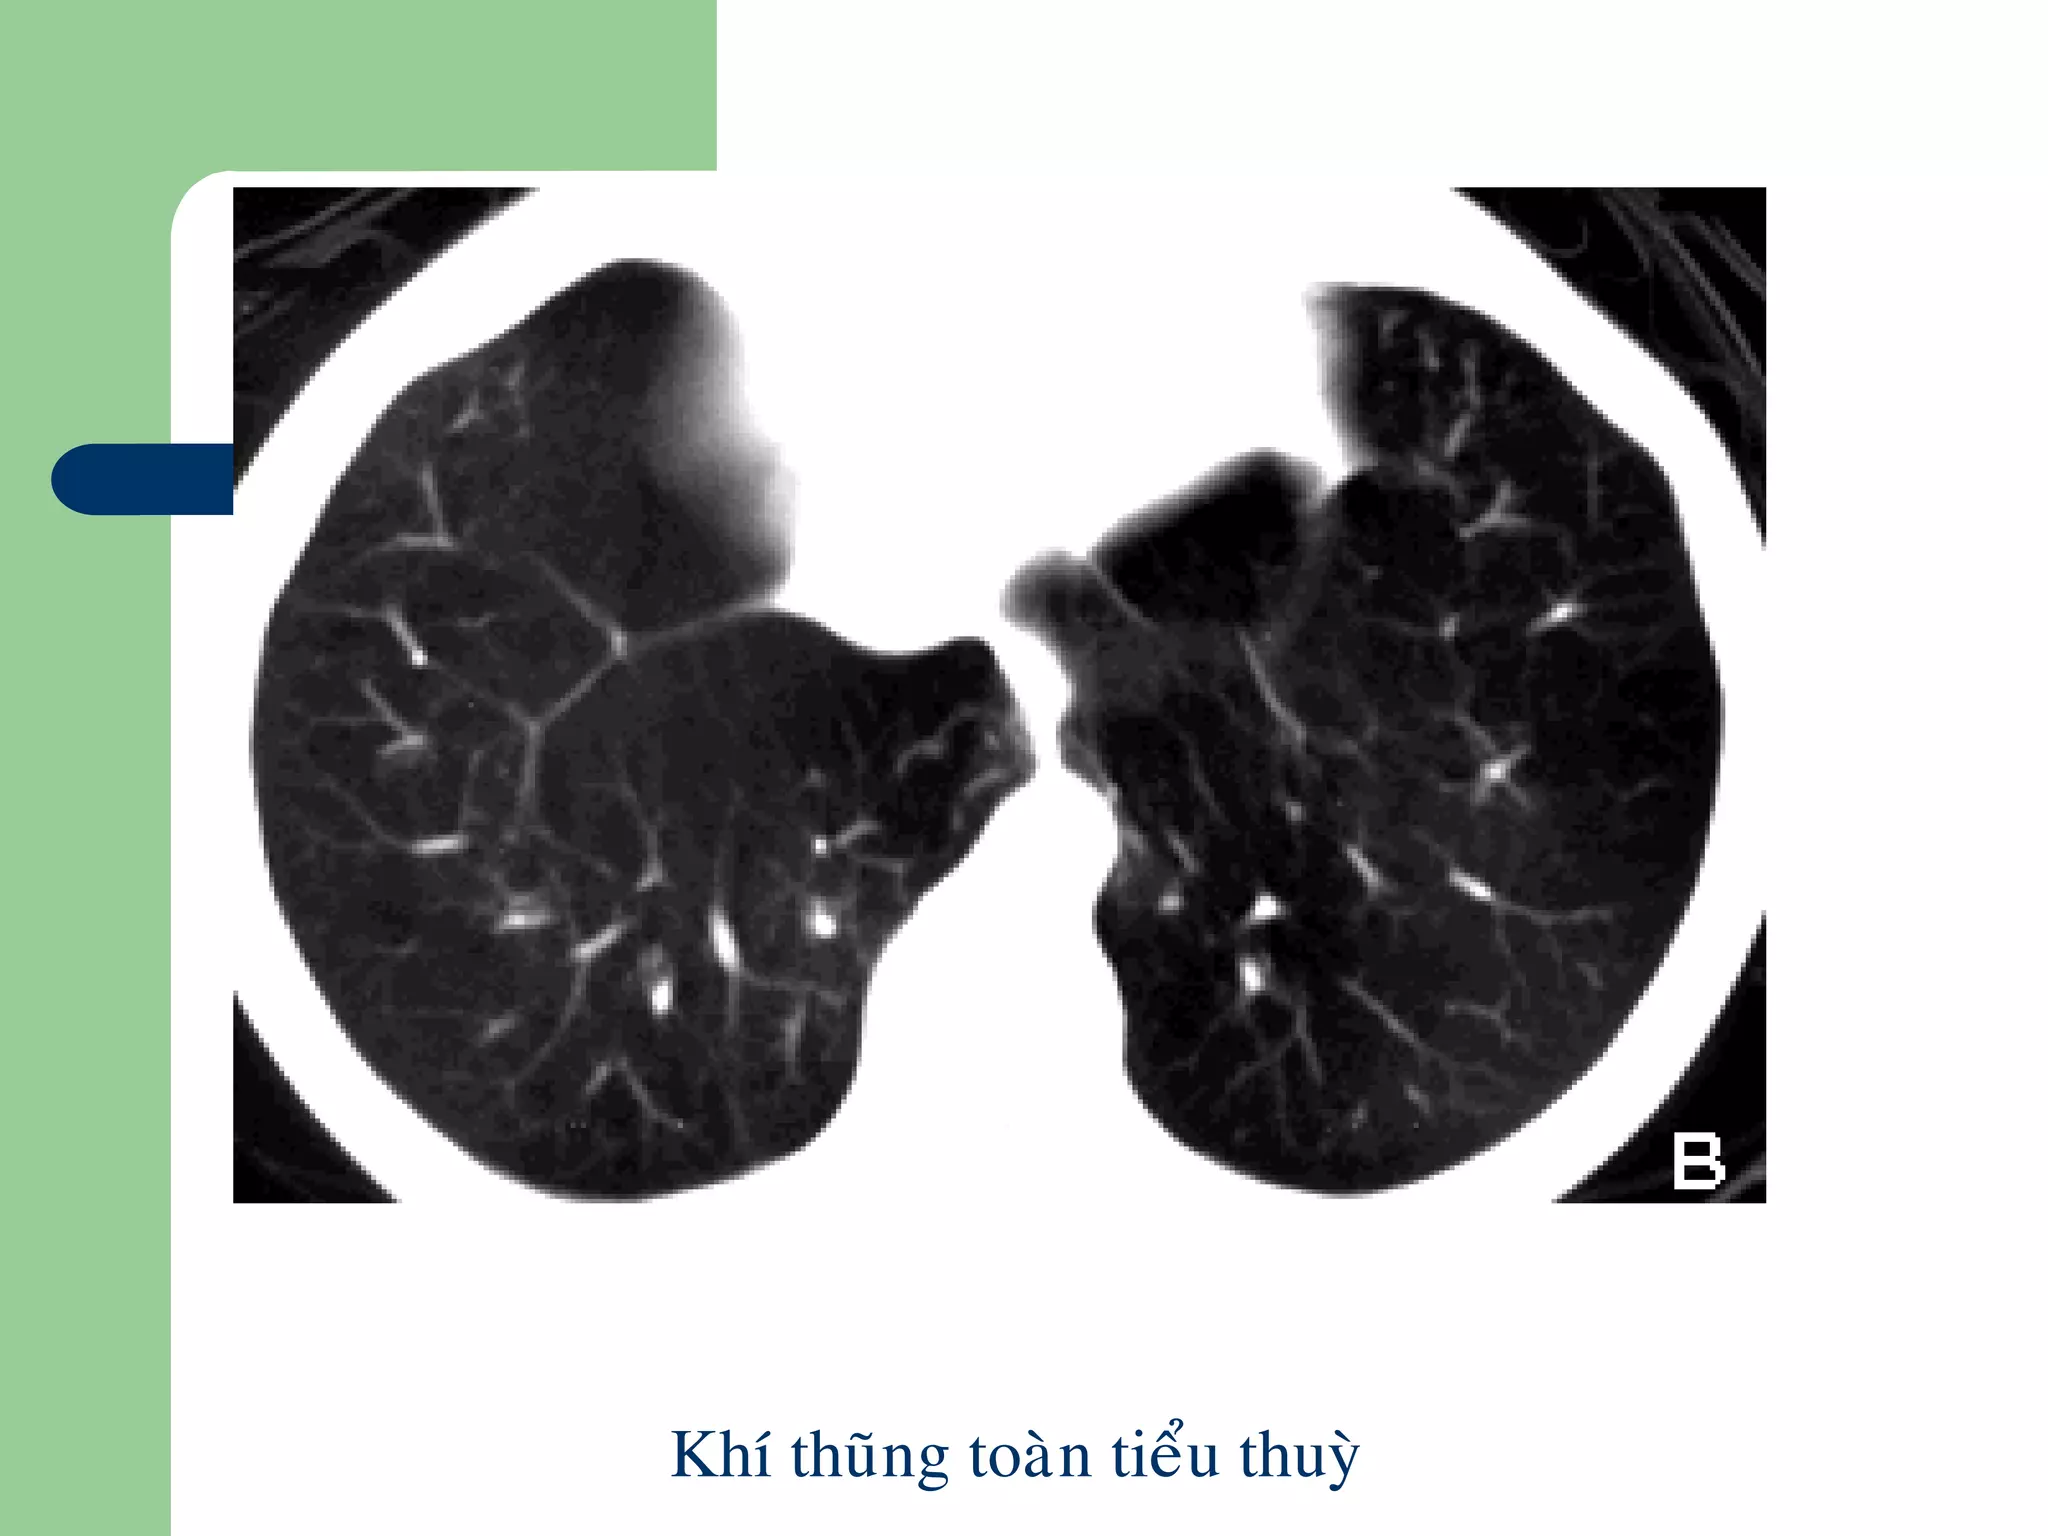

Khí thũng phổi

 Dãn lớn bất thường các khoảng chứa khí

ở phía xa của tiểu phế quản tận do hủy

thành phế nang và mạng lưới các sợi đàn

hồi

 CT: tạo các vùng giảm đậm độ với thành

bao quanh tổn thương không xác định rõ.

Gồm các dạng:

– Khí thũng trung tâm tiểu thùy (centrilobular

emphysema): vùng khí thũng quanh ĐM trung tâm

thùy phổi thứ cấp, hay gặp ở phần cao thùy giữa

– Khí thũng tòan bộ tiểu thùy (panlobular emphysema):

vùng khí thũng lan tỏa, đồng nhất, hay gặp ở thùy

dưới

Khí thuõng toaøn tieåu thuyø